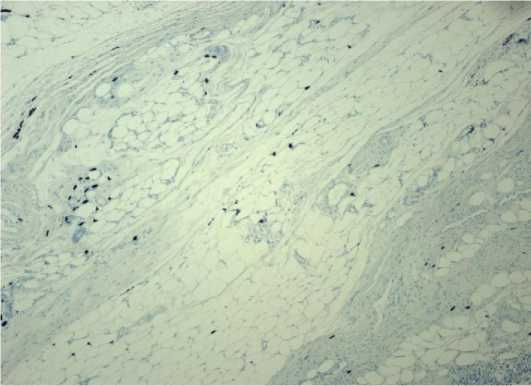

При детальном исследовании гистологических препаратов I группычетко визуализируется эпителиальный слой (рис. 1).

Но при этом наблюдается деструкция эпителиальных клеток, а в сохранившихся клетках – пикноз ядер. Компактный же слой выглядит как гомогенная бесклеточная оксифильная полоса, а местами в нем визуализируются волокна. Спон-гиозный слой также сохранен, но уплотнен, а структурная организация его потеряна. Толщина препаратов лиофилизированной амниотической мембраны с предварительным пропитыванием глицерином имеет среднее значение измерений (n=48) – 10,236 мкм.

Рисунок 1. Гистологический препарат амниотической мембраны, консервированной путем лиофилизации после предварительной обработки глицерином. Окраска ге-матоксилин-эозином. Ув. 400

Figure 1. Histological section of amniotic membrane preserved by lyophilization following glycerol pretreatment. Hematoxylin and eosin stain. Mag. 400